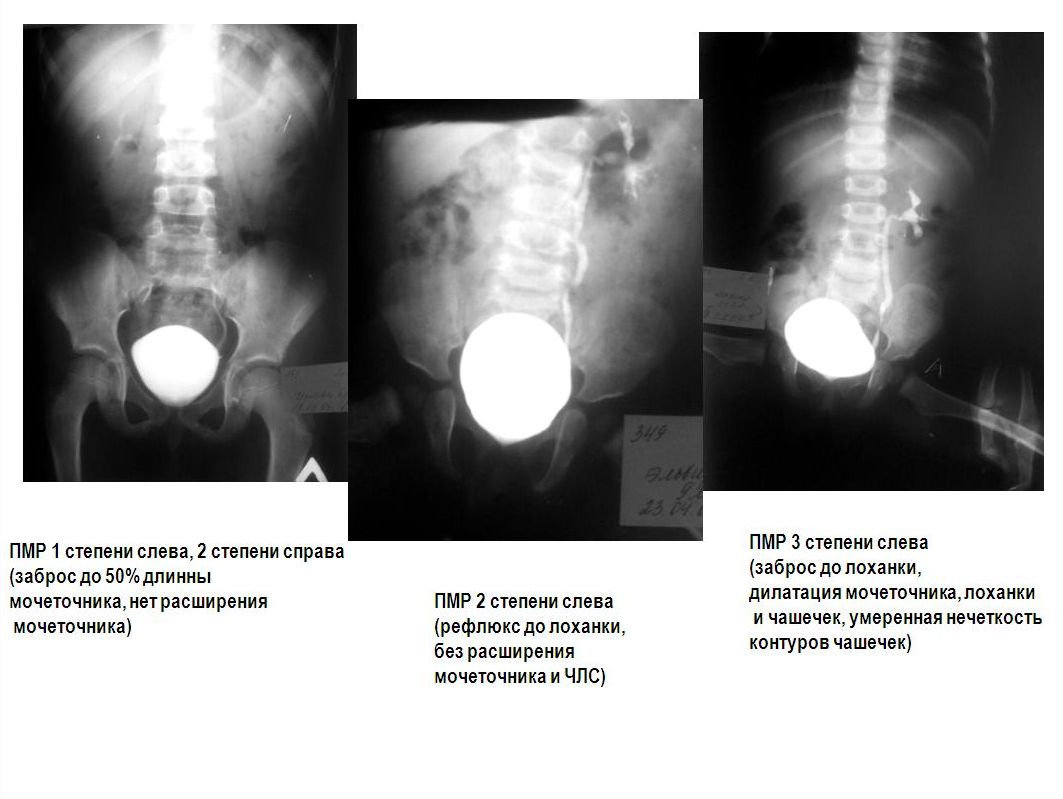

Медицинские изображения и примеры эксреторной цистографии